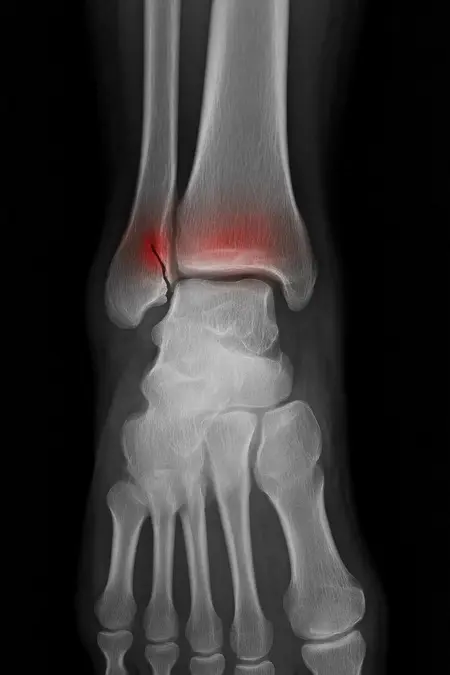

アートや写真の編集用に設計されたFlux Kontextのようなモデルを、医療画像、たとえば「単純な」骨折の赤色マーキングに使用できるか?

即答:面白い結果を出すが、過剰に反応し、医療ツールとしては信頼性に欠ける。これはアイデアを試すためのプロトタイプに過ぎない。

テスト結果:

- 偽陽性 ≈ 24%

- 骨折検出 ≈ 20%

感度モード(検出を優先、ノイズ多め)

- Euler、15ステップ、Karras

- Denoise:1.0

結果:

- 偽陽性 ≈ 80%

- 骨折検出 ≈ 86%

さらに攻撃的な設定(例:rk beta57、Denoise 1.0)では、**偽陽性100%、検出100%**という馬鹿げた結果に:すべてを赤で塗りつぶし、健常部もほぼすべて骨折と誤認する。未経験の目には区別がつかない。

Civitai用に作成した、100% AI生成の合成ミニデータセット(健康なX線10枚、骨折のあるX線10枚)でテスト:

- 健康な骨での偽陽性:100%

- 骨折検出:≈ 45%